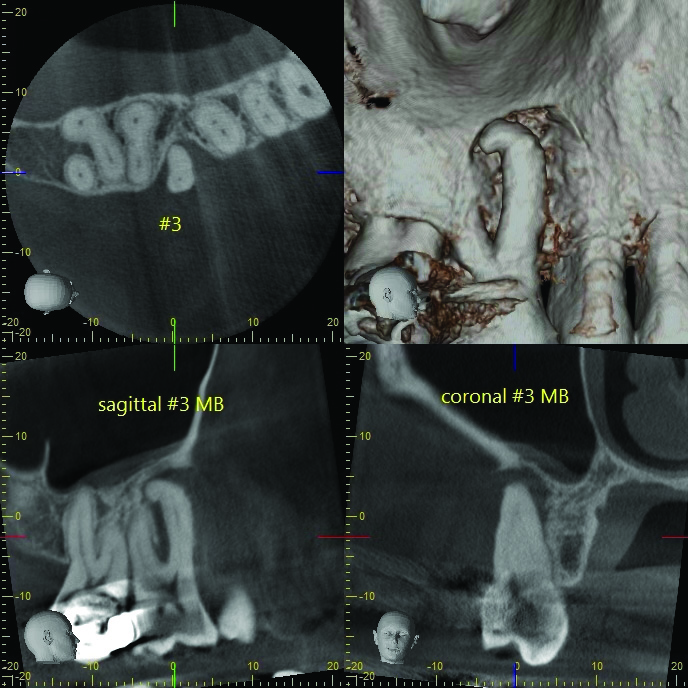

Fig 1 through Fig 4. Examples of multirooted teeth showing periradicular periodontitis and loss of periradicular bone support isolated to one root (indicated by red arrows). Fig 1: Tooth No. 3 distobuccal root with circumferential bone loss from the crestal bone height to the apex with stable mesiobuccal and palatal roots. Fig 2: Tooth No. 30 with a prior apical surgery showing bone loss surrounding a fractured mesial root. Fig 3: Tooth No. 19 with lateral and apical bone loss regions affecting a fractured mesial root. Fig 4: 3D CBCT imaging of tooth No. 3 depicting an apicomarginal bone loss defect affecting the mesiobuccal root with stable fused distobuccal and palatal roots.

Fig 4. Examples of multirooted teeth showing periradicular periodontitis and loss of periradicular bone support isolated to one root (indicated by red arrows). Fig 1: Tooth No. 3 distobuccal root with circumferential bone loss from the crestal bone height to the apex with stable mesiobuccal and palatal roots. Fig 2: Tooth No. 30 with a prior apical surgery showing bone loss surrounding a fractured mesial root. Fig 3: Tooth No. 19 with lateral and apical bone loss regions affecting a fractured mesial root. Fig 4: 3D CBCT imaging of tooth No. 3 depicting an apicomarginal bone loss defect affecting the mesiobuccal root with stable fused distobuccal and palatal roots.